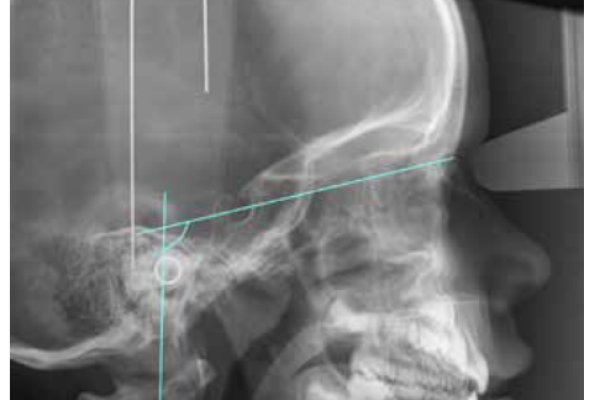

3 | ORIGINAL ARTICLE | CRANIOCERVICAL POSITION CHARACTERISTICS FOR DIFFERENT OCCLUSIONS IN DEVELOPING PATIENTS: CRANIOCERVICAL RELATIONSHIP AND OCCLUSION |